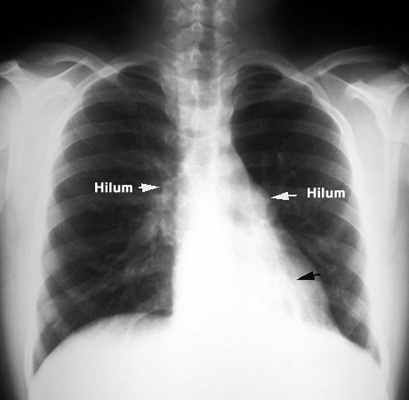

Localized Saccular BronchiectasisLeft hilum pulled down by the atelectatic left lower lobe. Retrocardiac tubular densities (hard to visualize). Bronchogram showing saccular bronchiectasis. Bronchograms are rarely done nowadays. CT can provide the diagnostic information. |